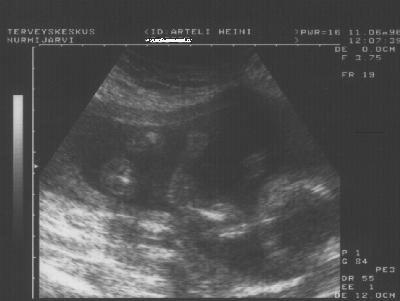

Hannu Matilda 5kk ennen syntymäänsä.